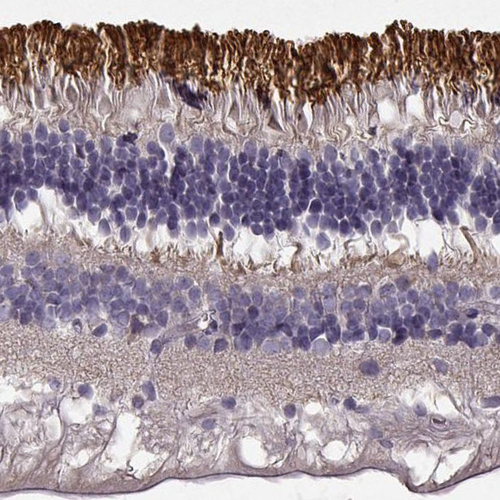

Immunohistochemical staining of human eye, retina shows strong cytoplasmic positivity in photoreceptor cells.